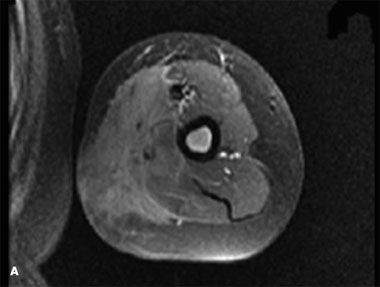

Before treatment, a repeated   MRI scan showed a large (15 X 4.5-   cm) mass medial to the humerus infiltrating   the biceps brachii, brachioradialis,   and triceps muscles with   extension into the subcutaneous fat.   The ulna neurovascular bundle, brachial   artery, and vein were all encircled   by the mass. On T-1 pulse sequence,   the mass was isointense to   the muscle with a normal bone cortex.   The bone marrow showed low   signal intensity, which signified an   infiltrative process. A T-1 fat-saturated   sequence revealed high signal intensity   of the bone marrow, related   to an absence of normal fatty bone   marrow. T-1 fat-saturated pulse sequence   postgadolinium injection   showed marked enhancement of the   soft tissue mass and bone marrow.

Virtually the entire humerus was involved,   with no cortical erosion (A).   ALL is one of the most common   malignancies in children, accounting   for 30% of all childhood   cancers.1,2 This primary malignancy   arises from bone marrow. It can occur in any age-group and is slightly   more common in girls in the first   decade of life, with a peak incidence   between 2 and 5 years. Leukemic   skin infiltrations can involve the epidermis,   dermis, and subcutaneous   fat. These lesions are seen in 1% of   patients.3